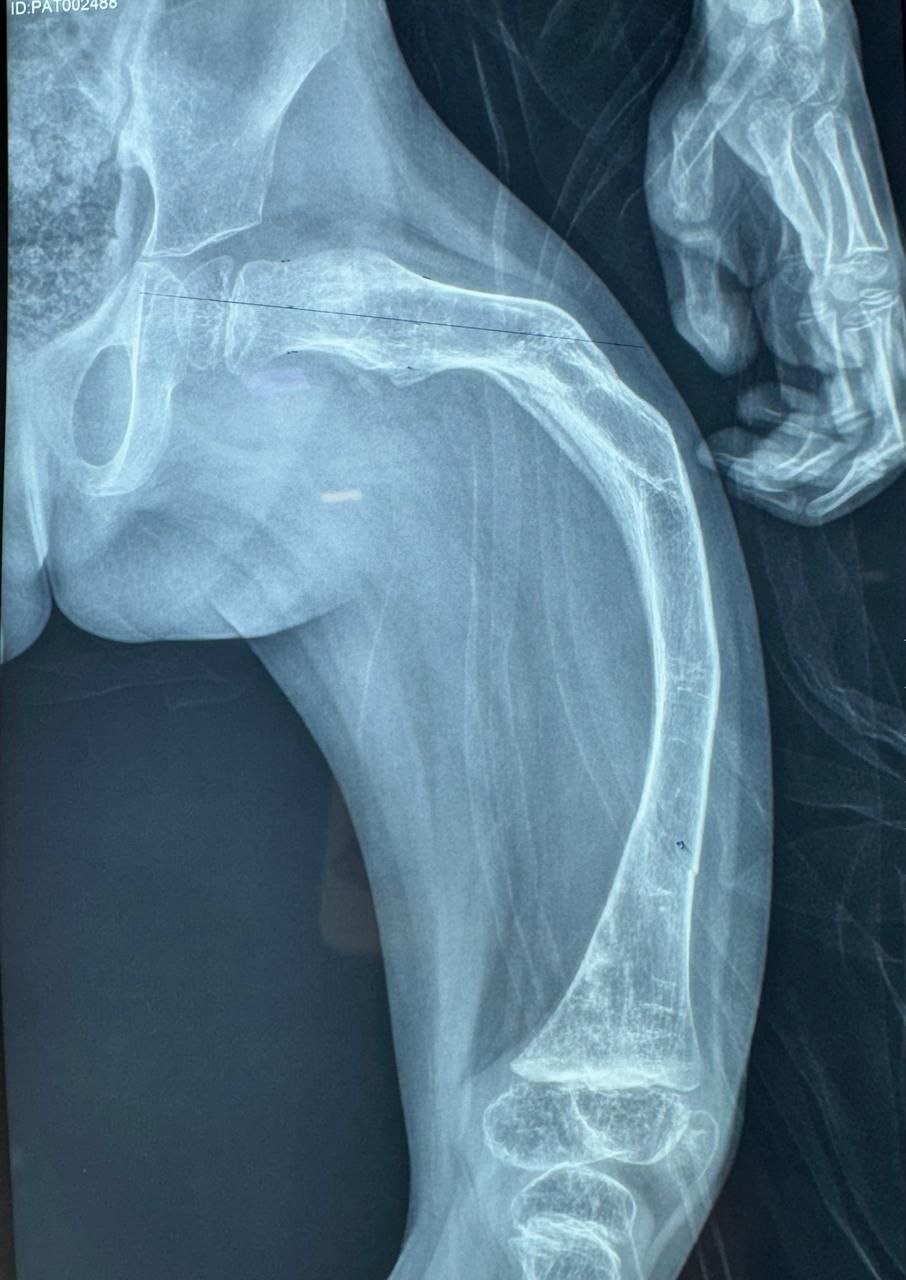

La ortopedia se enfoca en las enfermedades y alteraciones del sistema músculo-esquelético, tanto en adultos como en pacientes jóvenes. El Dr. Juan Carlos Torres Archila, especialista en ortopedia en Comitán, Chiapas, ofrece atención integral y personalizada para afecciones crónicas, degenerativas o congénitas que afectan huesos, articulaciones, músculos, tendones y ligamentos.

Cada caso es valorado a profundidad para proponer tratamientos conservadores (rehabilitación, ejercicios, ortesis) o procedimientos quirúrgicos cuando son necesarios, como artroplastías (colocación de prótesis articulares) o cirugías mínimamente invasivas como la artroscopía.